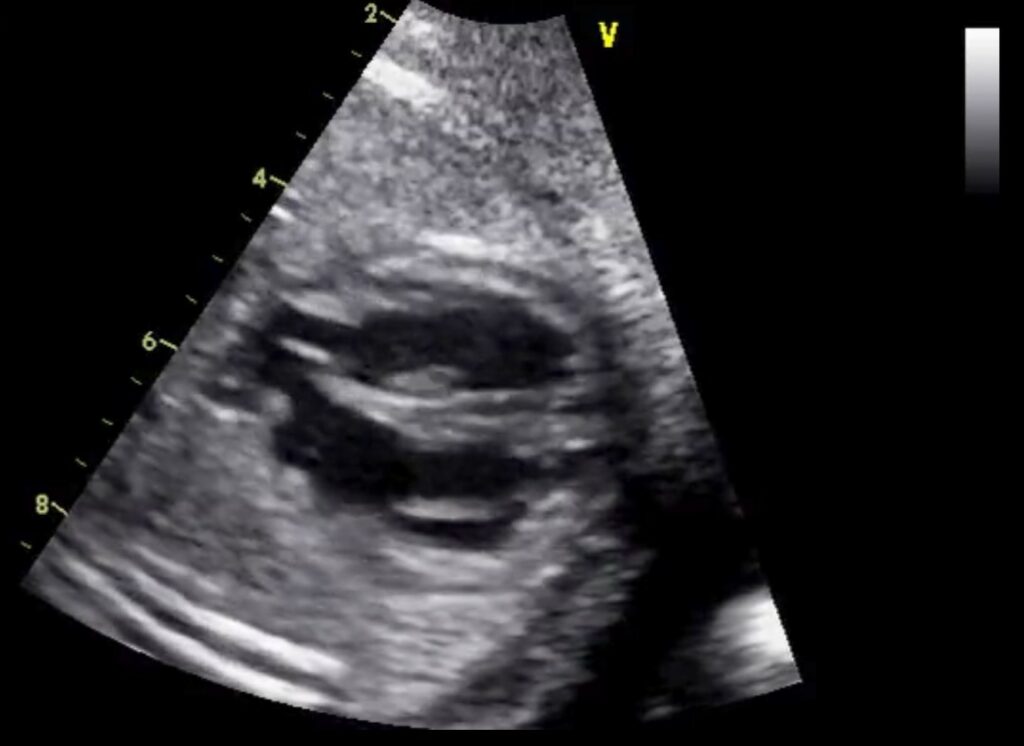

Si terrà il 9 e 10 novembre 2023 all’Auditorium L. Parenzan dell’ospedale Papa Giovanni XXIII di Bergamo un corso di formazione ed aggiornamento che punta a mettere in grado gli specialisti di riconoscere precocemente le anomalie cardiache fetali. Un centinaio i professionisti iscritti, da ogni parte d’Italia, tra medici cardiologi, anestesisti, ginecologi, neonatologi e ostetriche, che potranno fare pratica con le immagini delle ecocardiografie fetali. L’incontro vedrà come relatori tre medici considerati dalla comunità scientifica tra i maggiori esperti internazionali nel campo della diagnosi delle cardiopatie complesse.

Gli esperti internazionali hanno accettato l’invito dei colleghi del Papa Giovanni XXIII con cui esiste un rapporto scientifico di lunga data. L’ospedale di Bergamo ha una consolidata tradizione nel campo della cardiologia fetale e pediatrica. Un’attività clinica che è stata di recente rilanciata investendo in una nuova struttura complessa dedicata alla diagnosi e cura delle cardiopatie congenite fin dalla fase prenatale e perinatale.